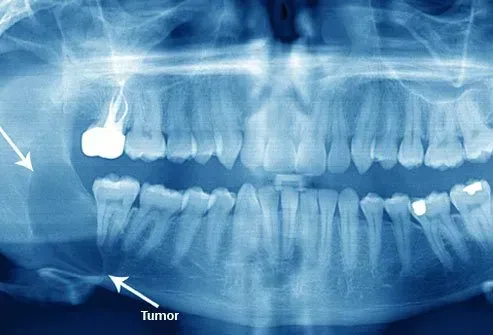

Kystes et tumeurs

Les dents de sagesse affectées sont particulièrement sujettes au développement de kystes et de tumeurs. Les kystes sont des sacs remplis de liquide qui peuvent se développer sur la mâchoire. Ils peuvent provoquer une perte osseuse dans votre mâchoire. Les tumeurs sont des croissances tissulaires anormales qui peuvent très rarement être cancéreuses.

Les kystes et les tumeurs peuvent devenir grands et douloureux qui causent potentiellement des problèmes dans votre bouche et même vos sinus s'ils sont non traités. Si un kyste ou une tumeur provoque des douleurs et d'autres problèmes autour de vos dents de sagesse, votre dentiste recommandera probablement de retirer ces dents. Heureusement, les kystes et les tumeurs associés aux dents de sagesse sont assez rares. Deux études ne les ont trouvées que dans environ 2,5% des dents de sagesse éliminées.